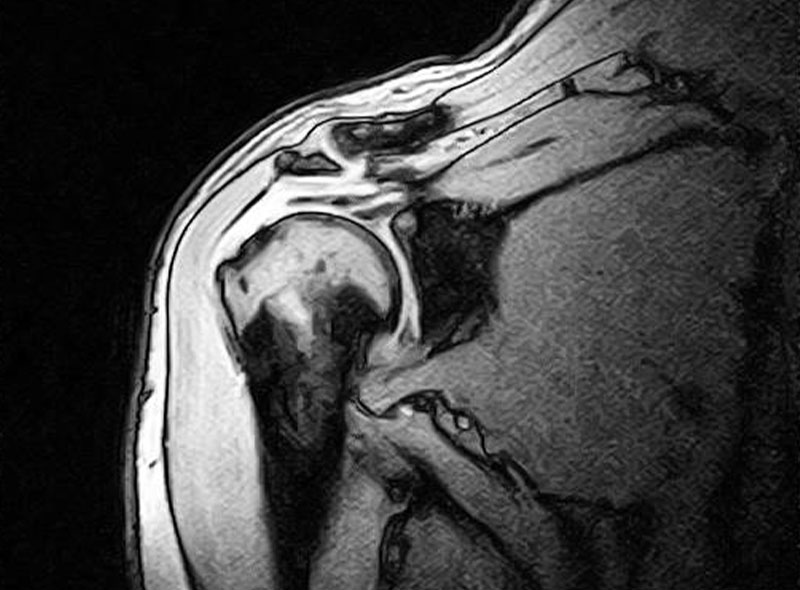

MRI

レントゲンでは判別困難な筋肉、靭帯などの軟部組織や微少骨折などの診断が放射線の被曝無しに行えるため安全で正確な検査が可能です。

当院の機器は開放型MRIであるため検査中の閉塞感が少なくなっています。

肩(腱板断裂)